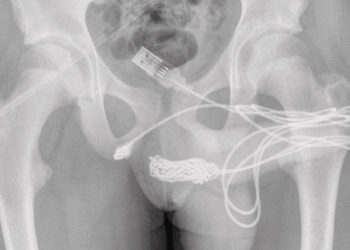

Read moreA UK-based teenager had to undergo emergency penis surgery after he somehow managed to insert a whole USB cable into...